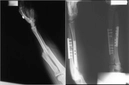

İt dirseği, genellikle dirsek ekleminde oluşan bir deformiteyi tanımlamak için kullanılan bir terimdir. Bu durum, genellikle aşırı kullanım, travma veya artrit gibi etkenlerle ortaya çıkar. İt dirseği ameliyatı, bu tür sorunları düzeltmek amacıyla uygulanan cerrahi bir müdahaledir. Bu makalede, it dirseği ameliyatının riskleri ve sonrasındaki iyileşme süreci üzerinde durulacaktır. İt Dirseği Nedir?İt dirseği, tıbbi literatürde "olekranon bursiti" olarak bilinir ve dirsek bölgesindeki bursanın iltihaplanması ile karakterizedir. Bu durum, genellikle aşırı yüklenme veya yaralanmalar sonucunda ortaya çıkar. Belirtileri arasında ağrı, şişlik ve hareket kısıtlılığı yer alır. İt Dirseği Ameliyatının Nedenleriİt dirseği ameliyatının yapılma nedenleri şunları içermektedir:

Bu riskler, cerrahın deneyimi, hastanın genel sağlık durumu ve ameliyat öncesi hazırlık süreçlerine bağlı olarak değişiklik gösterebilir. Ameliyat Sonrası İyileşme Süreciİt dirseği ameliyatından sonra, hastaların iyileşme süreci genellikle aşağıdaki adımları içerir:

İyileşme süreci, hastanın yaşı, genel sağlık durumu ve ameliyatın karmaşıklığına bağlı olarak değişiklik gösterebilir. Genellikle, hastalar birkaç hafta içinde günlük aktivitelerine dönebilir; ancak tam iyileşme süreci aylar alabilir. Sonuçİt dirseği ameliyatı, dirsek eklemindeki sorunları düzeltmek için etkili bir yöntemdir. Ancak, bu tür bir cerrahi müdahale öncesinde risklerin dikkatlice değerlendirilmesi ve hastanın durumuna uygun bir tedavi planının oluşturulması önemlidir. Ameliyat sonrası süreçte sabırlı olmak, fizik tedaviye uymak ve doktor tavsiyelerine dikkat etmek, başarılı bir iyileşme için kritik öneme sahiptir. Ekstra Bilgiler |